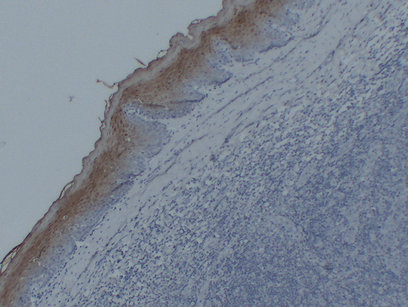

Immunohistochemistry analysis of paraffin-embedded Tonsil using Annexin A1 antibody.High-pressure and temperature Sodium Citrate pH 6.0 was used for antigen retrieval.